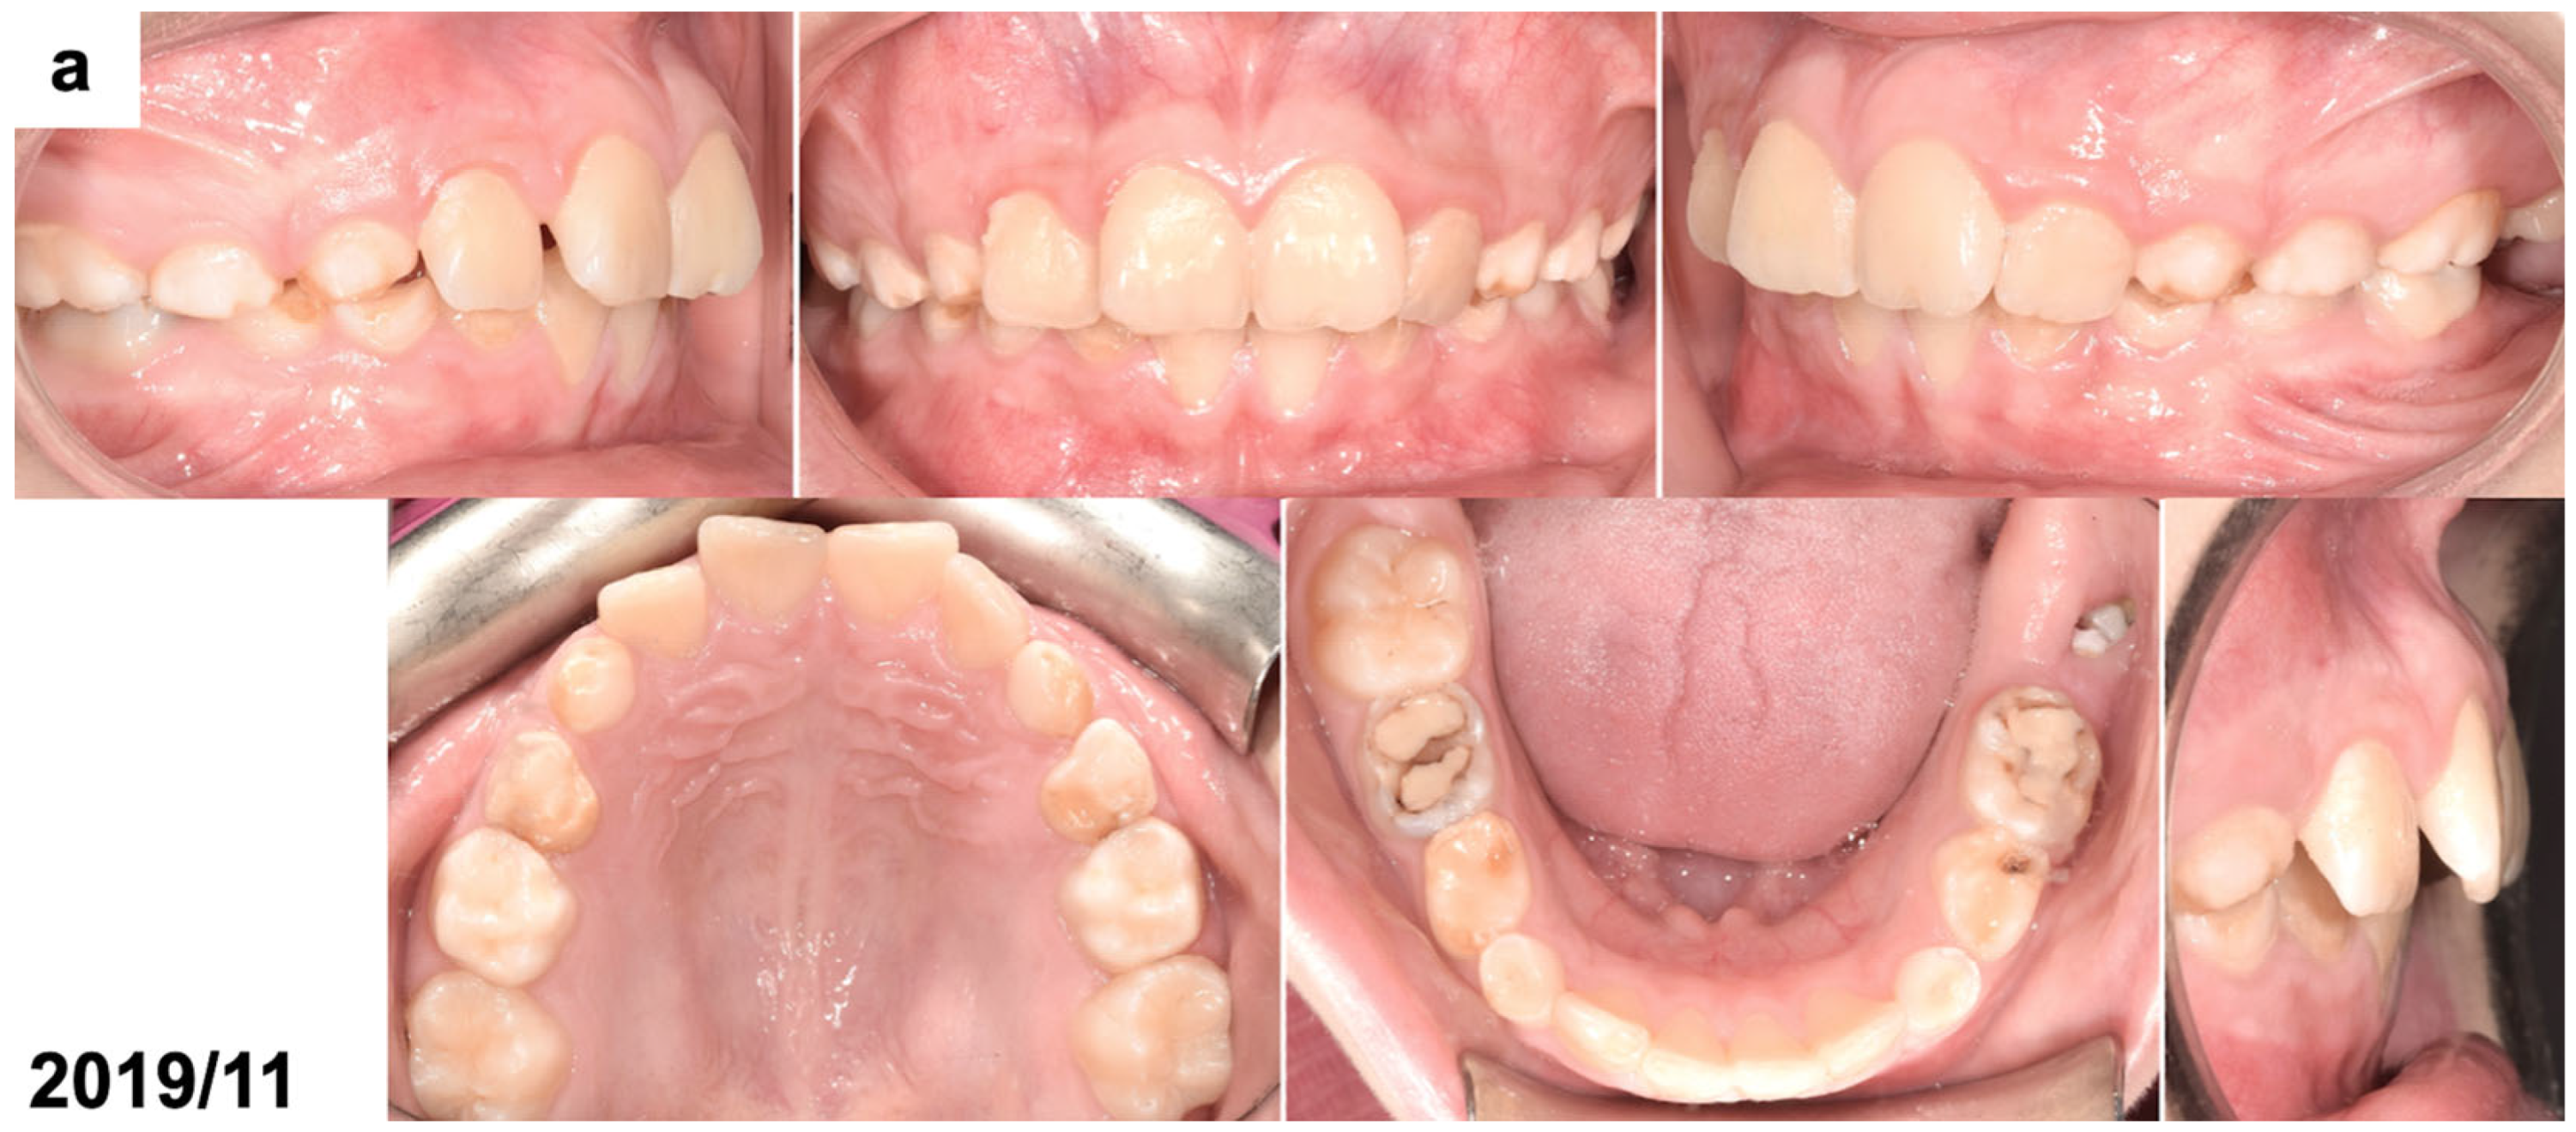

The patient’s face was symmetrical and proportional, and the profile was convex, with a slightly retruded chin. The lips were competent, and no oral dysfunctions or parafunctions were present. The patient was at the early mixed dentition period with all incisors and first permanent molars erupted, except for the mandibular left first molar. All deciduous canines and molars were present. The oral hygiene was poor, and the deciduous molars had large fillings. An extraoral examination revealed Class II dental relations with an increased overjet and overbite and a small space deficiency in the upper anterior segment. A small part of the clinical crown of the mandibular left first molar was visible through the gingiva (Figure 1a). Orthodontic documentation, including extraoral and intraoral photographs, diagnostic models, and a cephalometric radiograph, was taken before the start of the treatment. An extraoral examination revealed an enlarged, non-painful lymph node, differentiated with bone swelling by the lesion. The intraoral examination showed poor oral hygiene, teeth with numerous fillings and active caries, pathological abrasion, and no signs of soft tissue inflammation; the dimensions of the alveolar process were unchanged.

Figure 1.

(a) Intraoral photographs before surgical and orthodontic treatment. The patient was 8 years and 10 months old. (b) Panoramic radiograph before the treatment, presenting the odontogenic tumor in the left mandible molar region (OCx = complex odontoma). The patient was 8 years and 10 months old. (c,d) Intraoral photographs taken during the surgical removal of the tumor exposing the occlusal surface of the permanent lower left first molar (OCx = complex odontoma, LM1 = lower left first permanent molar). The patient was 8 years and 11 months old. (e) Panoramic radiograph after the surgical treatment and bonding of the orthodontic attachment (OA = orthodontic attachment). The patient was 8 years and 11 months old. (f) Panoramic radiograph 1 year after the removal of the tumor showing the orthodontic attachment bonded to the occlusal surface of the permanent lower left first molar (OA = orthodontic attachment). The patient was 10 years and 1 month old. (g) Intraoral photographs of spontaneously erupted permanent lower left first molar after removal of the orthodontic attachment. The patient was 10 years and 11 months old. (h) Panoramic radiograph 4 years after the surgical and orthodontic treatment (LM1 = lower left first permanent molar). The patient was 12 years and 7 months old. (i) Intraoral photographs 4 years after the surgical and orthodontic treatment showing the erupted permanent lower left first molar and its position in the dental arch. The patient was 12 years and 7 months old.

The panoramic radiograph (Figure 1b), which was provided by the patient, indicated the presence of a calcified lesion with a radiolucent rim and an adjacent cortical bone layer with a diameter of approx. 3 cm at the distal area of the mandibular first permanent molar. To precisely define the size and position of the tumor, the patient was referred for cone-beam computed tomography (CBCT). The CBCT examination showed a focal area with a calcified mass with the radiodensity of hard dental tissues surrounded by a narrow radiolucent zone on the left side in the molar region of the mandible. The dimensions of the lesion were 25 × 20 × 17 mm. The radiological picture indicated the presence of a complex odontoma. This lesion extended to the lower border of the mandible. The position of the neighboring first permanent molar was altered by the tumor as the tooth was moved downward and mesially. The roots of the affected molar were still developing (app. 2/3 of the final root length). The upper part of the tumor was not covered by the alveolar bone by 20 × 6 mm.